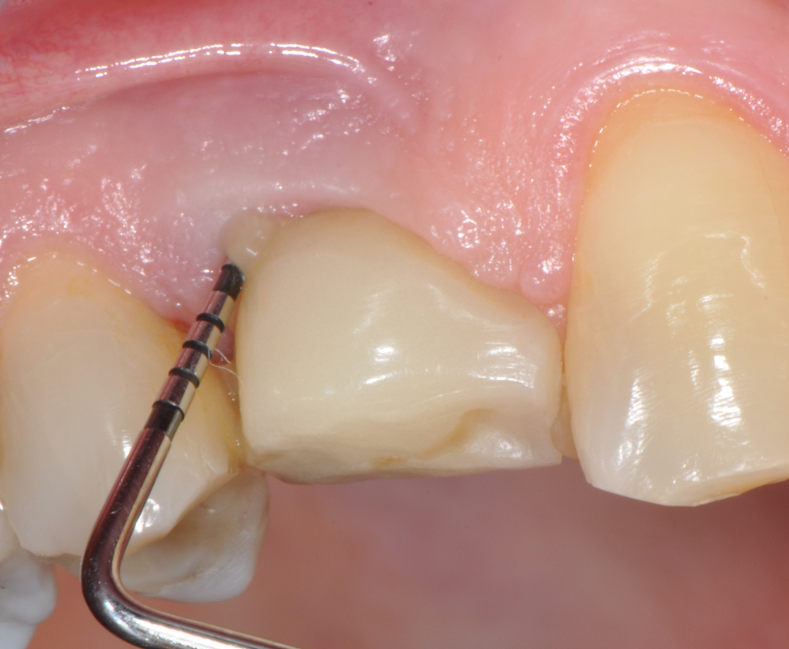

The parameters used to define peri-implant disease usually are: Probing Depth (PD), Crestal Bone Loss (CBL), Bleeding on Probing (BOP) and presence of suppuration and/or fistula.9 Peri-implant mucositis is characterised by soft tissues inflammation witnessed by BOP with or without PD deepening but no effects on the crestal bone while peri-implantitis is characterised by CBL, BOP alone or in conjunction with pus, with or without PD deepening. (Figs. 1, 2 and 3) display the diagnostic steps of a case of peri-implantitis. While mucositis allows a complete healing, peri-implantitis is not reversible.12

Crestal Bone Loss sets another ambiguous point because an adaptive change of the marginal bone level is known to occur afterimplantplacement and restoration.1It’s necessary to agree a baseline for the radiographic evaluation of bone level changes and set an acceptable bone loss rate. Basing on longitudinal clinical studies, it’s rational to chose the time of prosthesis installation as a reference from which the disease can be diagnosed and followed.14 Basing on Albrektson and Zarb review, 1.5mm of bone loss in the first year and less than 0.2mm annually are considered success criteria.1 A CBL exceeding this rate testifies the risk of implant failure. Don't forget that intra-oral x-rays allow to evaluate the interproximal bone level only, missing an appropriate vision of the buccal/lingual sides, where probing becomes essential. Bleeding on Probing is the key parameter for peri-implant disease diagnosis.13 Presence of BOP can be found in 91% of implants with peri-implantitis and its absence is regarded as a reliable predictive parameter of implant health.12

Fig.3: Case 1. X-ray testifying severe peri-implant CBL.